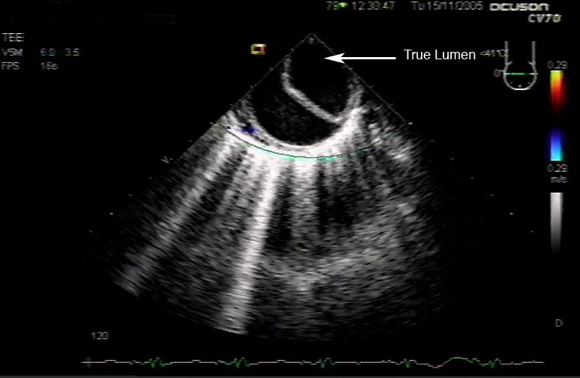

What does this refer to

Transesophageal echo Aortic Dissection